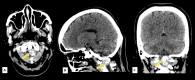

Figure 1

Figure 1. Plain cranial computed tomography (CT) scan in (A) axial, (B) sagittal, and (B) coronal views showing a well-defined extra-axial hyperdense mass with intralesional calcifications measuring 3.2x2.0x1.9 cm (CCxWxAP) within the spinal canal at the level of C1-C2 (arrow)

CC: Craniocaudal; W: Width; AP: Anteroposterior